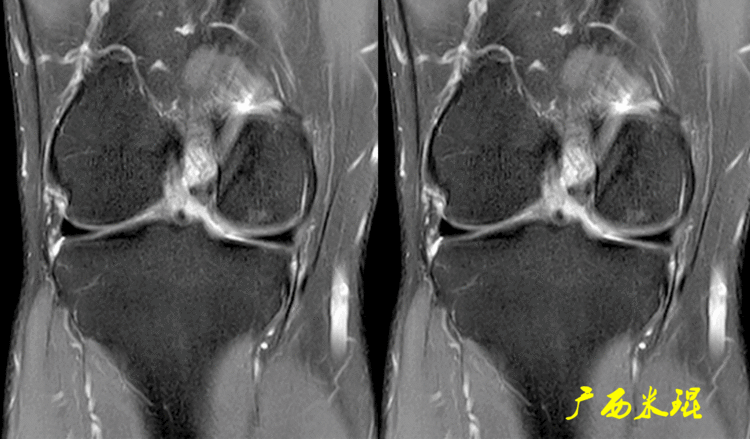

下面这张MR冠状位显示为内侧半月板后角的假桶柄,其母体(图片中内侧的那一部分半月板)并没有变小、形态及信号均正常。

下面这张MR冠状位显示为外侧半月板后角的假桶柄,尽管在髁间窝发现半月板信号,但其母体(图片中外侧的那一部分半月板)并没有变小、形态及信号均正常。